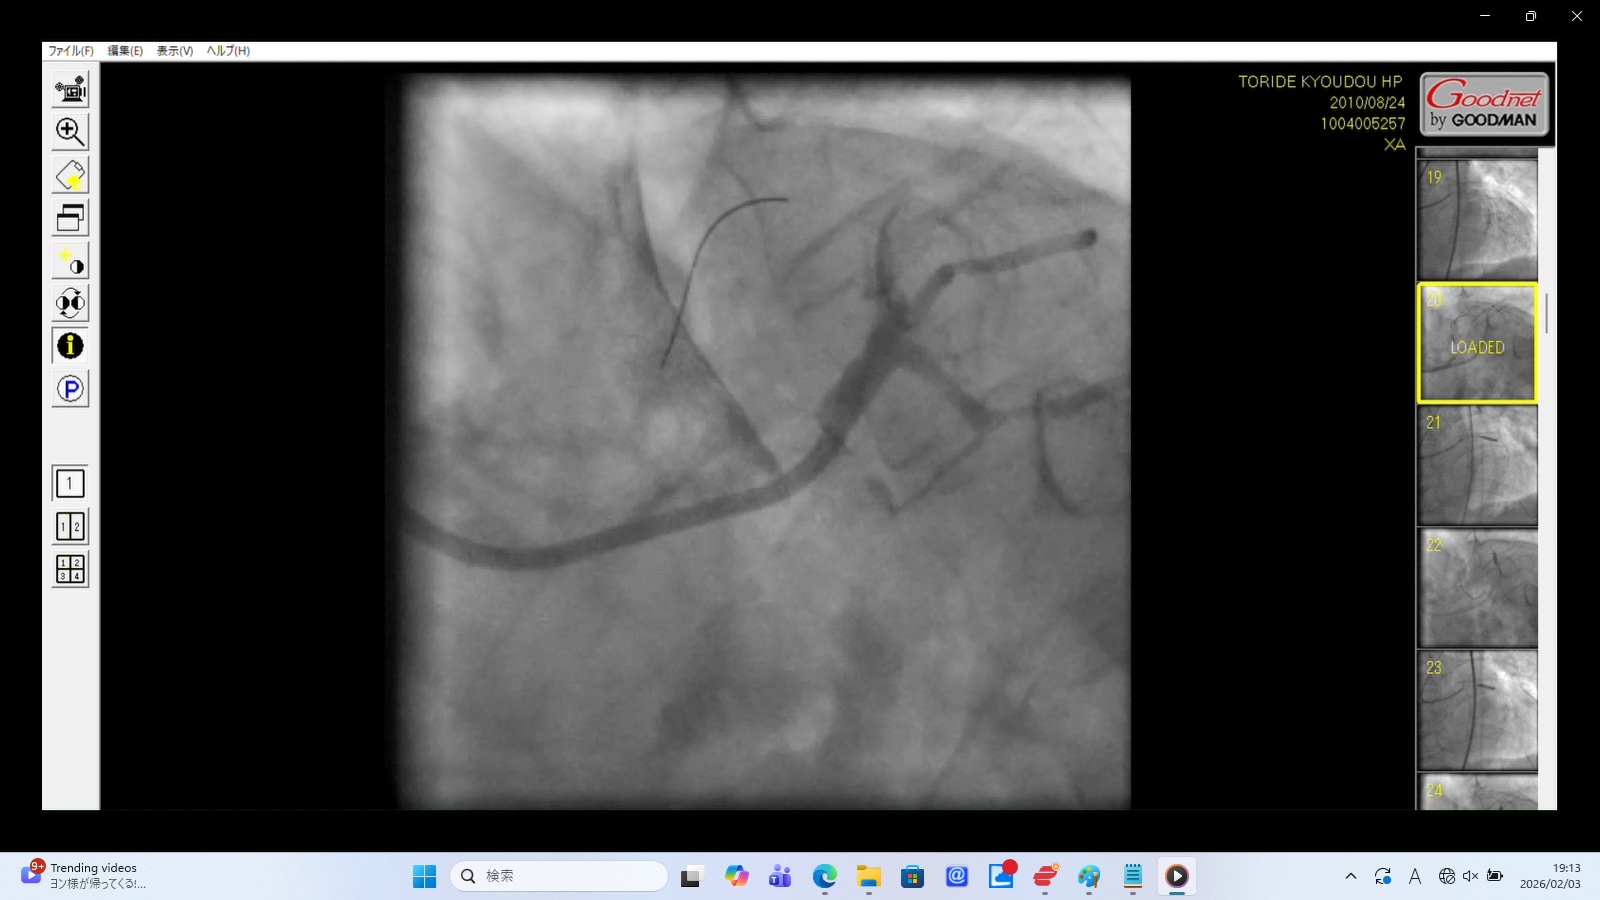

左前下行枝解離・穿孔、左冠動脈主幹部解離・損傷・完全閉塞、ステント様人工物の血管外脱落などの所見あり。 術者の岩井利之医師は「治療は成功した」と偽り、これらの大事故・大損傷を隠蔽した。救命のためには心臓血管外科での緊急手術が必要な状態であったはずだが、医師らはその手配をせず放置した。

血管外への広範な血液漏出と拡散

左冠動脈前下行枝(LAD)のリアルタイム解離

左冠動脈主幹部解離(真腔と偽腔の併存)と血管外漏出

22時35分に開始され、右橈骨動脈にガイドワイヤーを挿入して手技が開始されたが、 冠動脈にアプローチできず、右大腿動脈から挿入された。その間、アプローチが失敗した時間帯のPCI画像が 存在せず、ここで大事故を起こした証拠であるこの間の画像が抜き取られた可能性が疑われる。 PCIは3時間と長時間を要し、その間の放射線被曝量も人体に深刻な影響を与えるほど大量であった。 PCIの動画を確認すると左冠動脈主幹部解離・損傷・閉塞、左冠動脈前下行枝解離・穿孔、 左回旋枝への血栓閉塞、ステント様人工物の血管外落下など多数の致命的な大事故が認められた。 救命のためには心臓血管外科での開胸手術が必要のはずであったが、PCI終了後、医師は遺族に対して「治療は無事成功した」としてこの大事故を隠蔽し、心臓血管外科への手配をせずに放置し談笑していた。